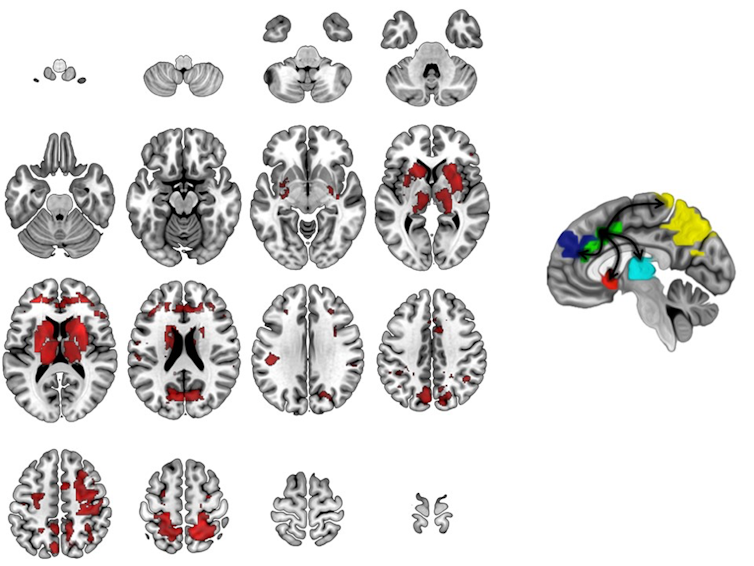

Our laboratory has used brain MRI studies to help unlock the underlying anatomy, chemistry and physiology underlying OCD. This repetitive, ritualistic illness – while sometimes used among laypeople to describe someone who is uptight – is actually a serious and often devastating behavioral illness that can paralyze children and their families.

Through sophisticated, high-field brain imaging techniques – such as fMRI and magnetic resonance spectroscopy – that have become available recently, we can actually measure the child brain to see malfunctioning areas.

We have found, for example, that children 8 to 19 years old with OCD never get the “all clear signal” from a part of the brain called the anterior cingulate cortex. This signal is essential to feeling safe and secure. That’s why, for example, people with OCD may continue checking that the door is locked or repeatedly wash their hands. They have striking brain abnormalities that appear to normalize with effective treatment.

We have also begun a pilot study with a pair of identical twins. One has OCD and the other does not. We found brain abnormalities in the affected twin, but not in the unaffected twin. Further study is clearly warranted, but the results fit the pattern we have found in larger studies of children with OCD before and after treatment as compared to children without OCD.

New, more sophisticated brain imaging and genetics technology actually allows doctors and scientists to see what is going on in a child’s brain and genes. For example, by using MRI, our laboratory discovered that the brain chemical glutamate, which serves as the brain’s “light switch,” plays a critical role in childhood OCD.